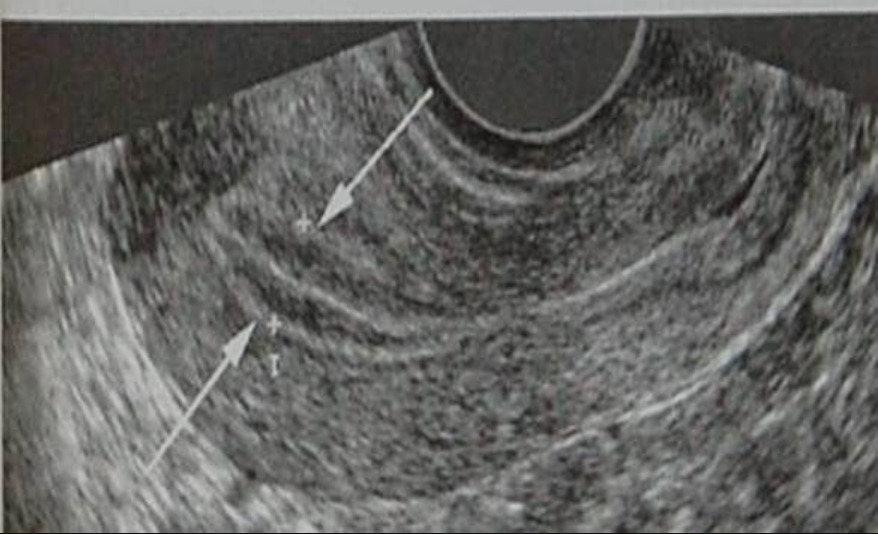

Niêm mạc tử cung dày ảnh hưởng rất nhiều đến khả năng thụ thai của phụ nữ. Lời khuyên là phụ nữ không nên tự chẩn đoán về tình trạng niêm mạc tử cung của mình để rồi dẫn đến những lo lắng không cần thiết, tự tạo áp lực cho bản thân. Thông qua hình ảnh và các chỉ số trên siêu âm, các bác sĩ mới có thể chẩn đoán chính xác độ dày niêm mạc tử cung là bình thường hay bất thường. Hãy tham khảo tư vấn của bác sĩ để biết thêm về các xét nghiệm thăm khám cần thiết cho chẩn đoán cũng như được tư vấn cụ thể về phương pháp điều trị phù hợp. Thư giãn tâm lý và làm theo chỉ định của bác sĩ là một trong những cách hữu hiệu giúp chị em phụ nữ sớm có con trong cuộc sống của mình.